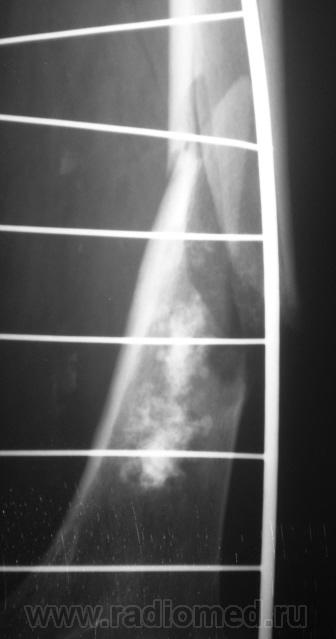

Ну, и, после "репозиции".

н\3 бедра со смещением по длине и ширине. Отломки находятся под углом открытым кпереди прим. в 10-15 град.

После репозиции дистальный отломок смещён латерально на ширину кортикального слоя.

А не создается-ли впечатления, что представленный перелом патологический? Первый снимок произведен через час после травмы.

костных структур в проекции прелома, то действительно это патологический перелом. Честно не сразу обратил внимание.

Что это - не скажу (под рукой нет литературы). Но. 1.Процесс опухолевый - в средней части, по заднему контуру отмечается вздутие кости. 2.Относительно длительно текущий - вздутие достаточно протяженное. 3.Пока еще относительно доброкачественный - кортикальный слой созранен. 4. Многоузловой (мультифокальный) - не менее 3-х узлов/фокусов. В зависимости от возраста/пола/анамнеза вполне может быть метастатическим. 5.Перелом все-таки патологический - линия перелома проходит через верхнюю часть патологического субстрата.

Это может оказаться и безобидным обызвествлением костного мозга после инфаркта, хондромой или хондросаркомой. - Уроки Татьяны Валентиновны. Но вздутия не вижу - его в боковой проекции симулирует третий фрагмент в месте перелома. Ну а метастаз - маловероятен... Опять же - "горим" на сочетанной патологии...

Как по мне, так там наоборот, локальное (хотя и на достаточном протяжении) УТОЛЩЕНИЕ кортикального слоя по задней поверхности, хотя и в сочетании с умеренным вздутием.

Данная рентген-картина может быть характерна и для хондросаркомы.

Вот, и у меня зародилась такая подлая мысль о наличии "хондро", и даже очень вероятно хондросаркомы.

хочу поддержать доктора Анатолия Шумакова: перелом вряд ли патологический, обызвествление костного мозга бедренной кости и вероятно стенок сосудов